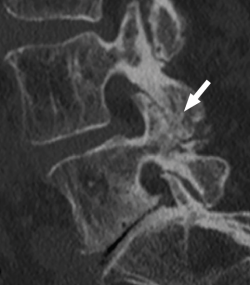

Figura 12. Tomografía axial computarizada de hernia discal. Reproducido de Gaillard(26).

Entre las principales indicaciones de la TAC, se incluirían la sospecha clínica de hernia discal (Figura 12)(26), la estenosis del canal vertebral lumbar, la fractura vertebral lumbar, los tumores vertebrales, la valoración posquirúrgica tras una cirugía de artrodesis vertebral lumbar y la sospecha de una sacroileitis en el contexto clínico de una posible espondiloartropatía inflamatoria. También es muy útil como herramienta auxiliar en determinados procesos diagnósticos, como por ejemplo en la biopsia de una zona sospechosa y en el diagnóstico postoperatorio de la correcta colocación de implantes en la columna vertebral.